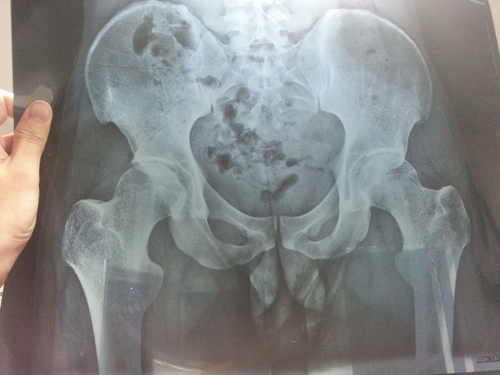

2、胯骨疼是股骨头坏死比较典型的症状之一

当出现了股骨头坏死的时候,一般也会让您右边胯骨疼,在这个时候,一定要去医院进行治疗。

去医院做个CT ,非常有必要,检查一下你的髋关节是否有病变,一般人不会有这种情况的,这关系到你的将来的健康,不是小问题,大意不得哦!